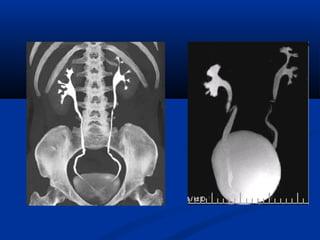

Xaùc ñònh vò tríxöông söôøn treân CT